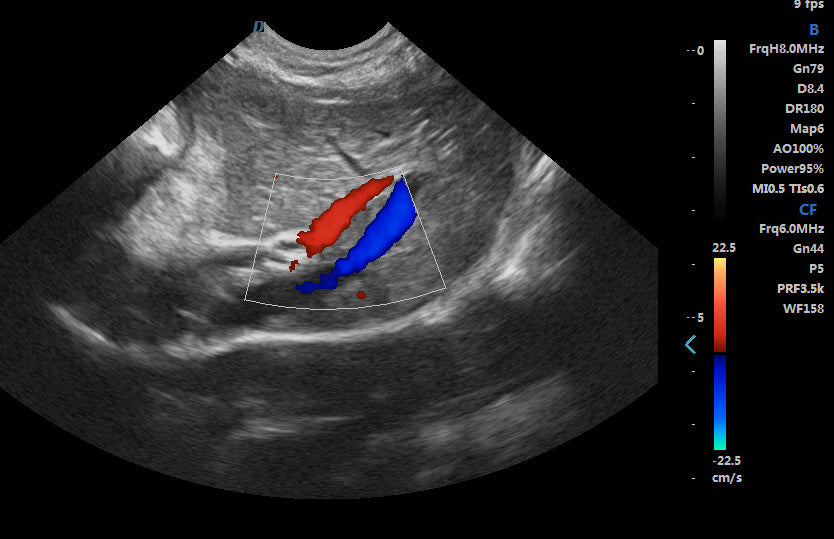

2. Excellent image processing functions, including spectral pulse Doppler, directional energy Doppler, spatial composite imaging, and tissue harmonic imaging technology.

Spectral Pulse Doppler

Directional Energy Doppler

Real-time Triplex

3. Support real-time three-dimensional imaging function, the maximum number of focal points is 6 focal points, frame correlation is 0-4 levels, trapezoidal imaging function, multi-beam parallel processing, etc.

6. The application range is very wide, including universities, research institutions on the rat heart and cranial, vascular blood flow, tumor detection, thrombus detection; experimental institutions on the rabbit blood vessel detection, real-time detection of blood flow, heart function, rabbit tumor detection; widely used in pet hospitals, pet clinics, pet stores, zoos, abdominal organs, superficial organs, heart, blood flow effects, etc.; fish The technology of checking fish roe/white/bubble/gonad, etc., for sturgeon egg size, fullness and egg quality control.